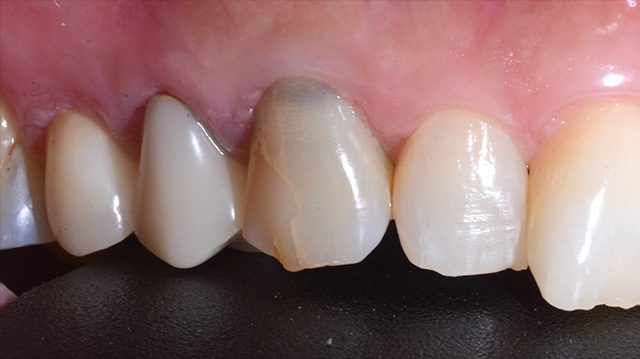

| 年代・性別 | 50代 男性 |

|---|---|

| 主訴 | 転倒して歯が割れた |

| 治療回数 | 3回 |

| 治療期間 | 約1ヶ月 |

| 費用 | 仮歯 5,500円 ジルコニアクラウン 176,000円 |